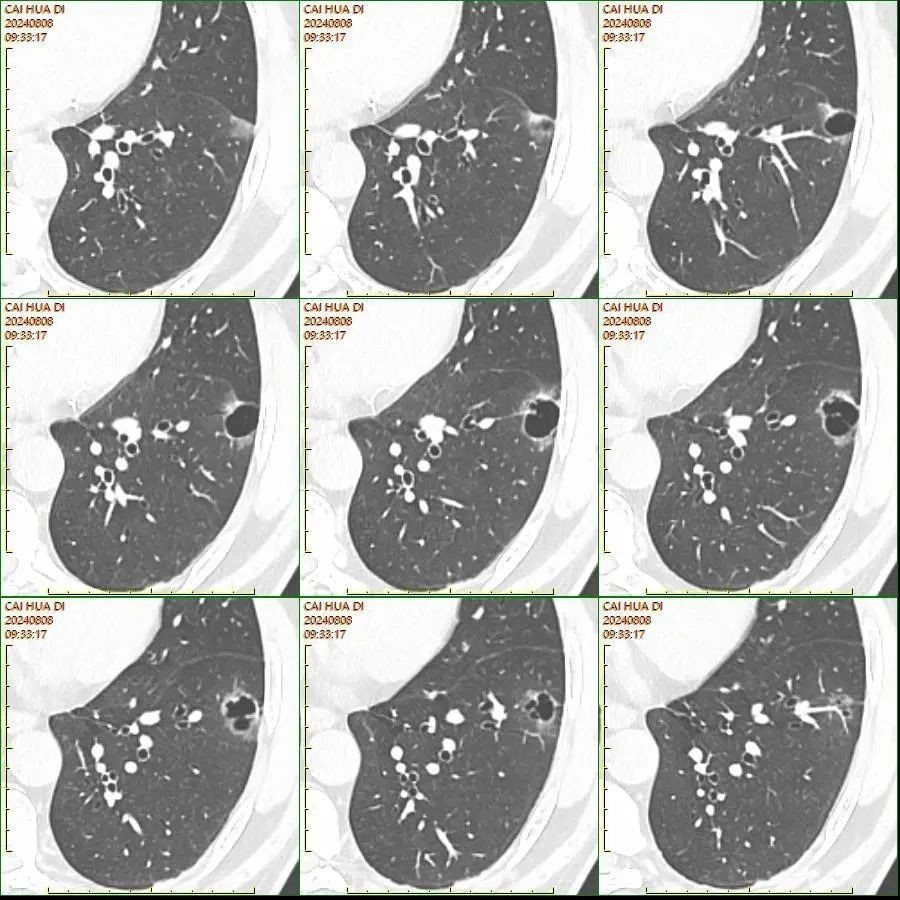

64岁的蔡叔(化名)因冠心病到茂名市人民医院例行体检,没想到,这一次却同时揪出了藏在身体里的两个“恶魔”——他的肺部以及肾脏均发现了不明肿物,经过被誉为“火眼金睛”PET-CT的细致检查,这两处肿物考虑为“左下肺癌合并右肾癌”。

▲术前左下肺囊腔型结节CT与三维重建图